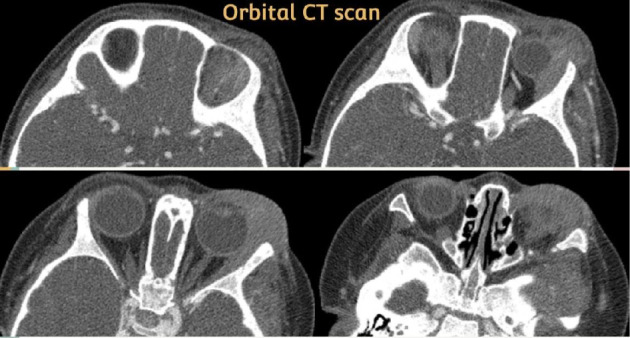

A 19-month-old female with Down syndrome presented with recurrent left cheek swelling and left eye involvement, initially diagnosed as fasciitis/myositis and periorbital cellulitis. Despite empiric antibiotics, symptoms persisted. A whole-body CT scan revealed prominent lymph nodes, and a biopsy of the buccal mass showed myeloid sarcoma. Bone marrow aspiration confirmed acute myeloid leukemia. Following chemotherapy, the patient's symptoms resolved. This case underscores that acute leukemia may manifest as facial swelling or periorbital cellulitis, highlighting the importance of considering extramedullary myelosarcoma in cases of persistent, unexplained soft tissue swelling that does not respond to standard treatments.